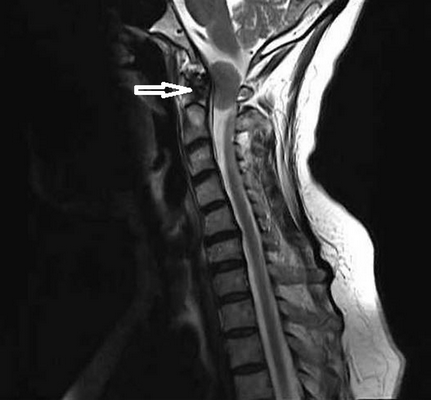

Учитывая темп развития симптомов, был заподозрен злокачественный характер опухоли. В день поступления (02.03.16) пациентке выполнена МРТ головного мозга и спинного мозга с контрастным усилением. Была выявлена диссеминация процесса с появлением опухоли в левом внутреннем слуховом проходе, множественных очагов патологического накопления контрастного вещества оболочек спинного мозга. Динамика распространения первичного очага и метастазирование представлены на рис. 1 и 2.

Рис 2. МРТ от 02.03.2016 - метастазирование опухоли по оболочкам спинного мозга (указаны стрелками).